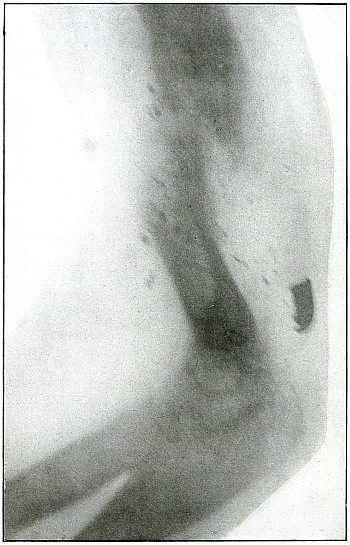

Projectiles.—The projectiles which figure in the illustrations

In describing the plates the terms used in connection with range are

(1) Close range, from 0 to 100 yards.

(3) Mid range, from 500 to 1,000 yards.

The wound effects of the modern military rifle bullet at various

(1) Explosive range, from 0 to 500 yards.

(3) Penetrating range, from 1,500 to 2,500 yards.